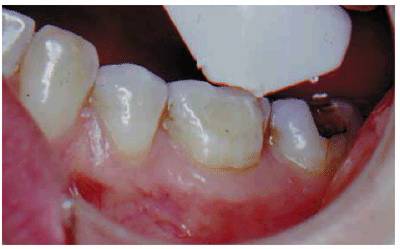

teeth is difficult at best and impossible with most. It has been suggested that

if root structure is exposed owing to gingival recession, the

"mini-tip" that comes with the Vitality Scanner should be used (Figure 19-15). Unfortunately, this is not a very

accurate method because there is a significant likelihood that the periodontal

ligament would respond to the stimulus, giving the false impression that the

pulp is still vital. The mini-tip, when used in conjunction with a prepared

test cavity or a small opening in a cast crown (Figures 19-16A, and 19-16B), is quite advantageous. This tip

is placed directly through the opening and onto the exposed dentin. Care should

be taken to keep the electrolyte (toothpaste or fluoride gel) from touching the

metal of the casting.

Figure 19-16A: Access through porcelain and metal to the dentin.

Figure 19-16B: Mini-tip placed on dentin through prepared cavity.